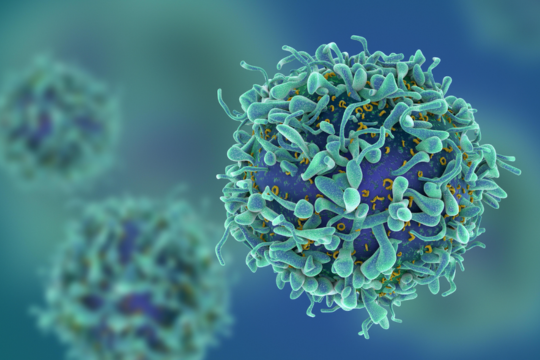

Testing for tailored cancer treatment

Empowering cancer research through innovation

A new era of oncological data

Transforming cancer care through liquid biopsy